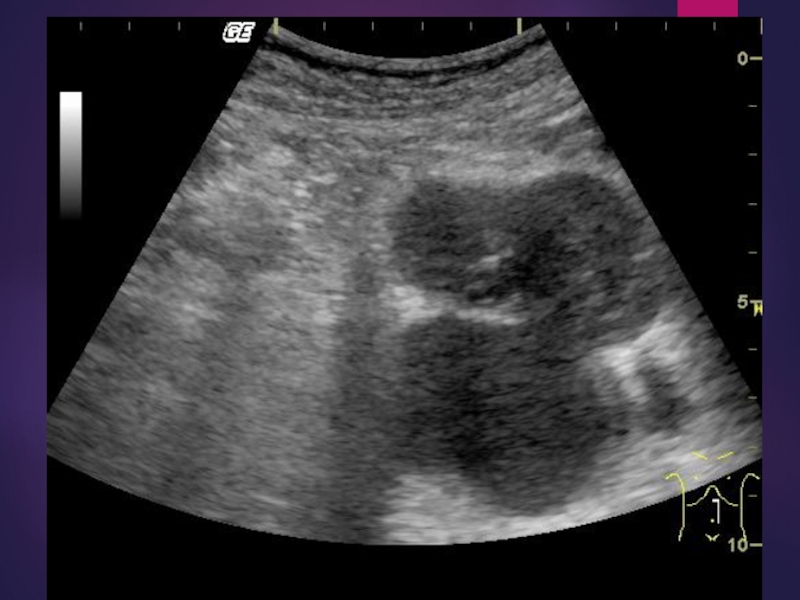

Слайд 8УЗИ поджелудочной железы

определяют воспалительные заболевания, аномалии развития, хронический и острый

панкреатит  и его осложнения, неопухолевые (кисты, жировая инфильтрация) и опухолевые

доброкачественные и злокачественные поражения.

УЗИ поджелудочной железы определяют воспалительные заболевания, аномалии развития, хронический и острый панкреатит  и его осложнения, неопухолевые (кисты, жировая